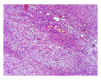

Neurofibroma is a benign peripheral nerve sheath tumor comprising variable mixture of Schwann cells, perineurial-like cells, and fibroblasts. Neurofibroma may occur as solitary lesion or as part of a generalised syndrome of neurofibromatosis or very rarely as multiple neurofibromas without any associated syndrome. There are two distinct variants of neurofibromatosis type I and type II. We present a case of neurofibroma of the hard palate associated with neurofibromatosis type I. The diagnosis of the lesion was made based on the clinical findings, family history, histopathology, and immunohistochemistry. Literature was reviewed and different types of neurofibroma, their incidence and frequency in the oral cavity, its association with neurofibromatosis, clinical manifestations, histopathologic characteristics, immunohistochemical analysis, behaviour, treatment, and recurrence are discussed.